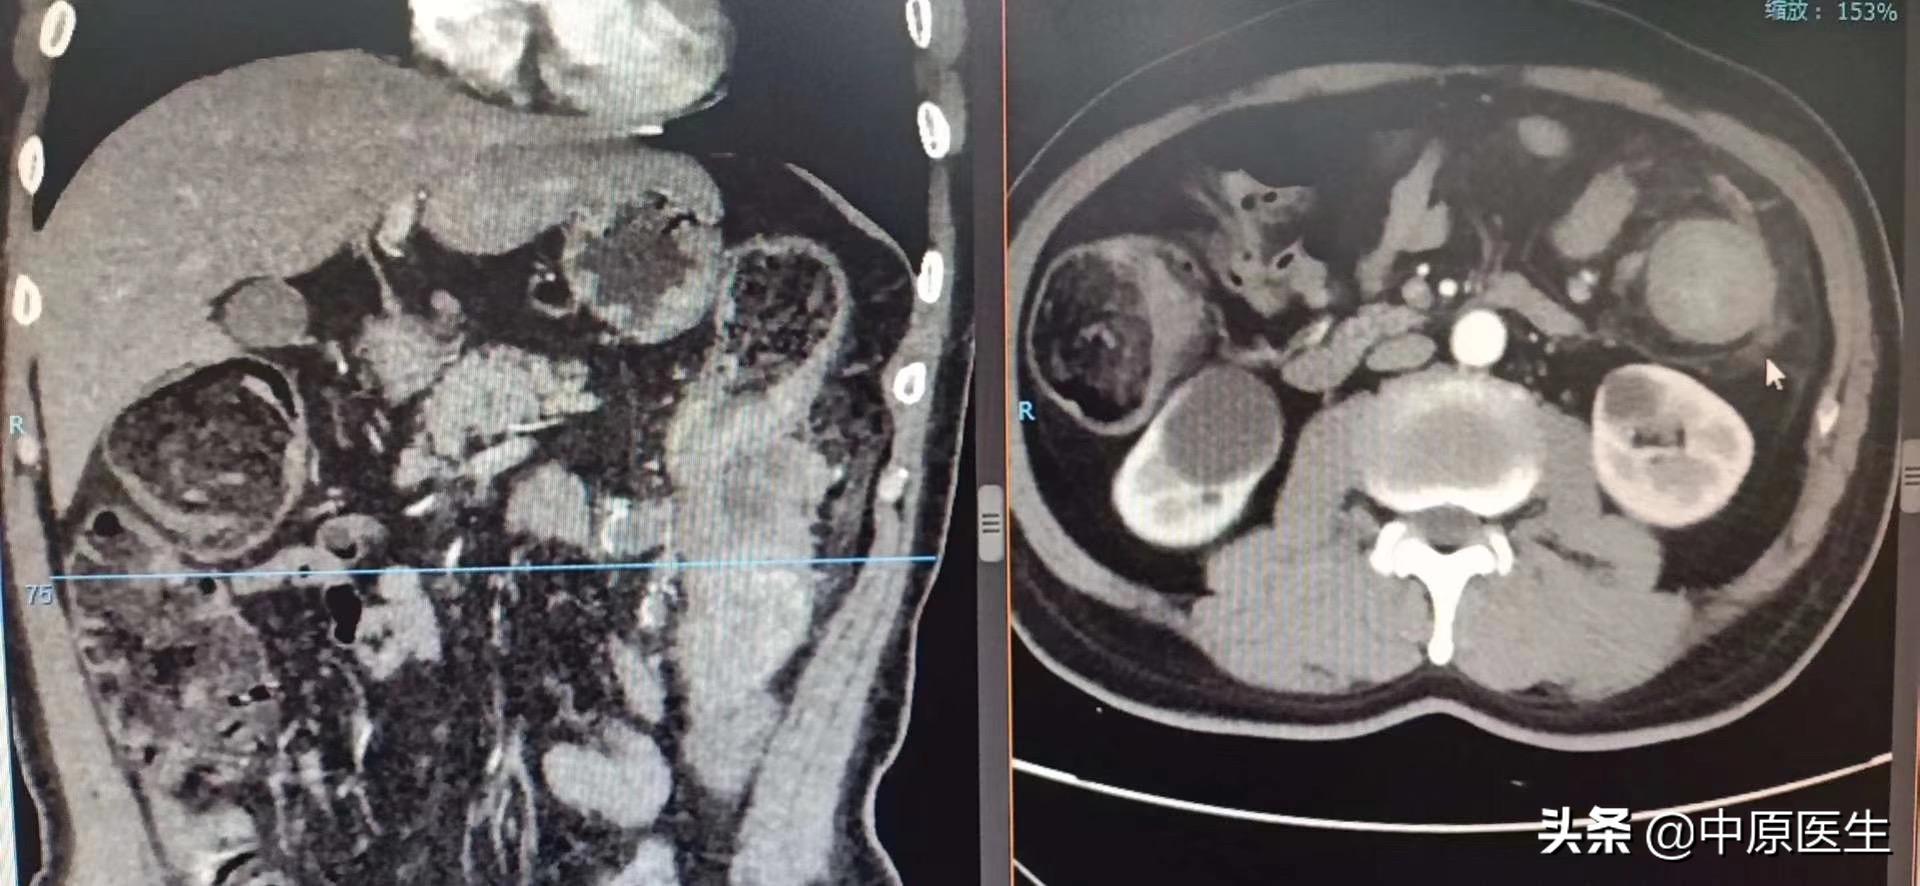

近1周来,患者腹胀进行性加重,体检发现患者腹胀如鼓。做腹部、盆腔ct:降结肠占位较前增大、重度狭窄,横结肠以上明显扩张、梗阻。经对症治疗效果欠佳,究竟该怎么办?

经过会诊,我们介入科刘建文教授团队决定通过介入方法帮助患者解决肿瘤引起梗阻的问题。25日,在导管室行局麻下消化道造影+降结肠球囊扩张+经肛型肠梗阻导管置入术。术中透视见腹部膨大,肠管明显扩张,膈肌上移。让患者取截石位仰卧,充分润滑、局麻后,我们送入超滑导丝、直径不到1mm的导管,反复尝试导丝通过闭塞处、送至横结肠脾曲处,但导管无法跟进,为了保留150cm的超滑导丝,将100cm的直径不到1mm导管分段剪断、依次撤出,再送入直径2mm的指引导管,再送入一根260cm的超滑加硬导丝,送至横结肠内,依次用10mm球囊、肠梗阻导管的扩张器反复扩张狭窄处,肠梗阻导管仍无法通过,再次同轴送入双导丝,应用16mm球囊多次扩张后,顺利把肠梗阻导管送至横结肠内,充盈导管头端球囊,将肠梗阻导管头端固定于降结肠梗阻处上方;淤积的肠气和部分肠液、粪便排入引流袋内,病人腹胀减轻。术中反复交换各种导丝、导管,带出不少臭屁、臭粪便。整个手术间都是不可描述的气味、手术台不忍直视。